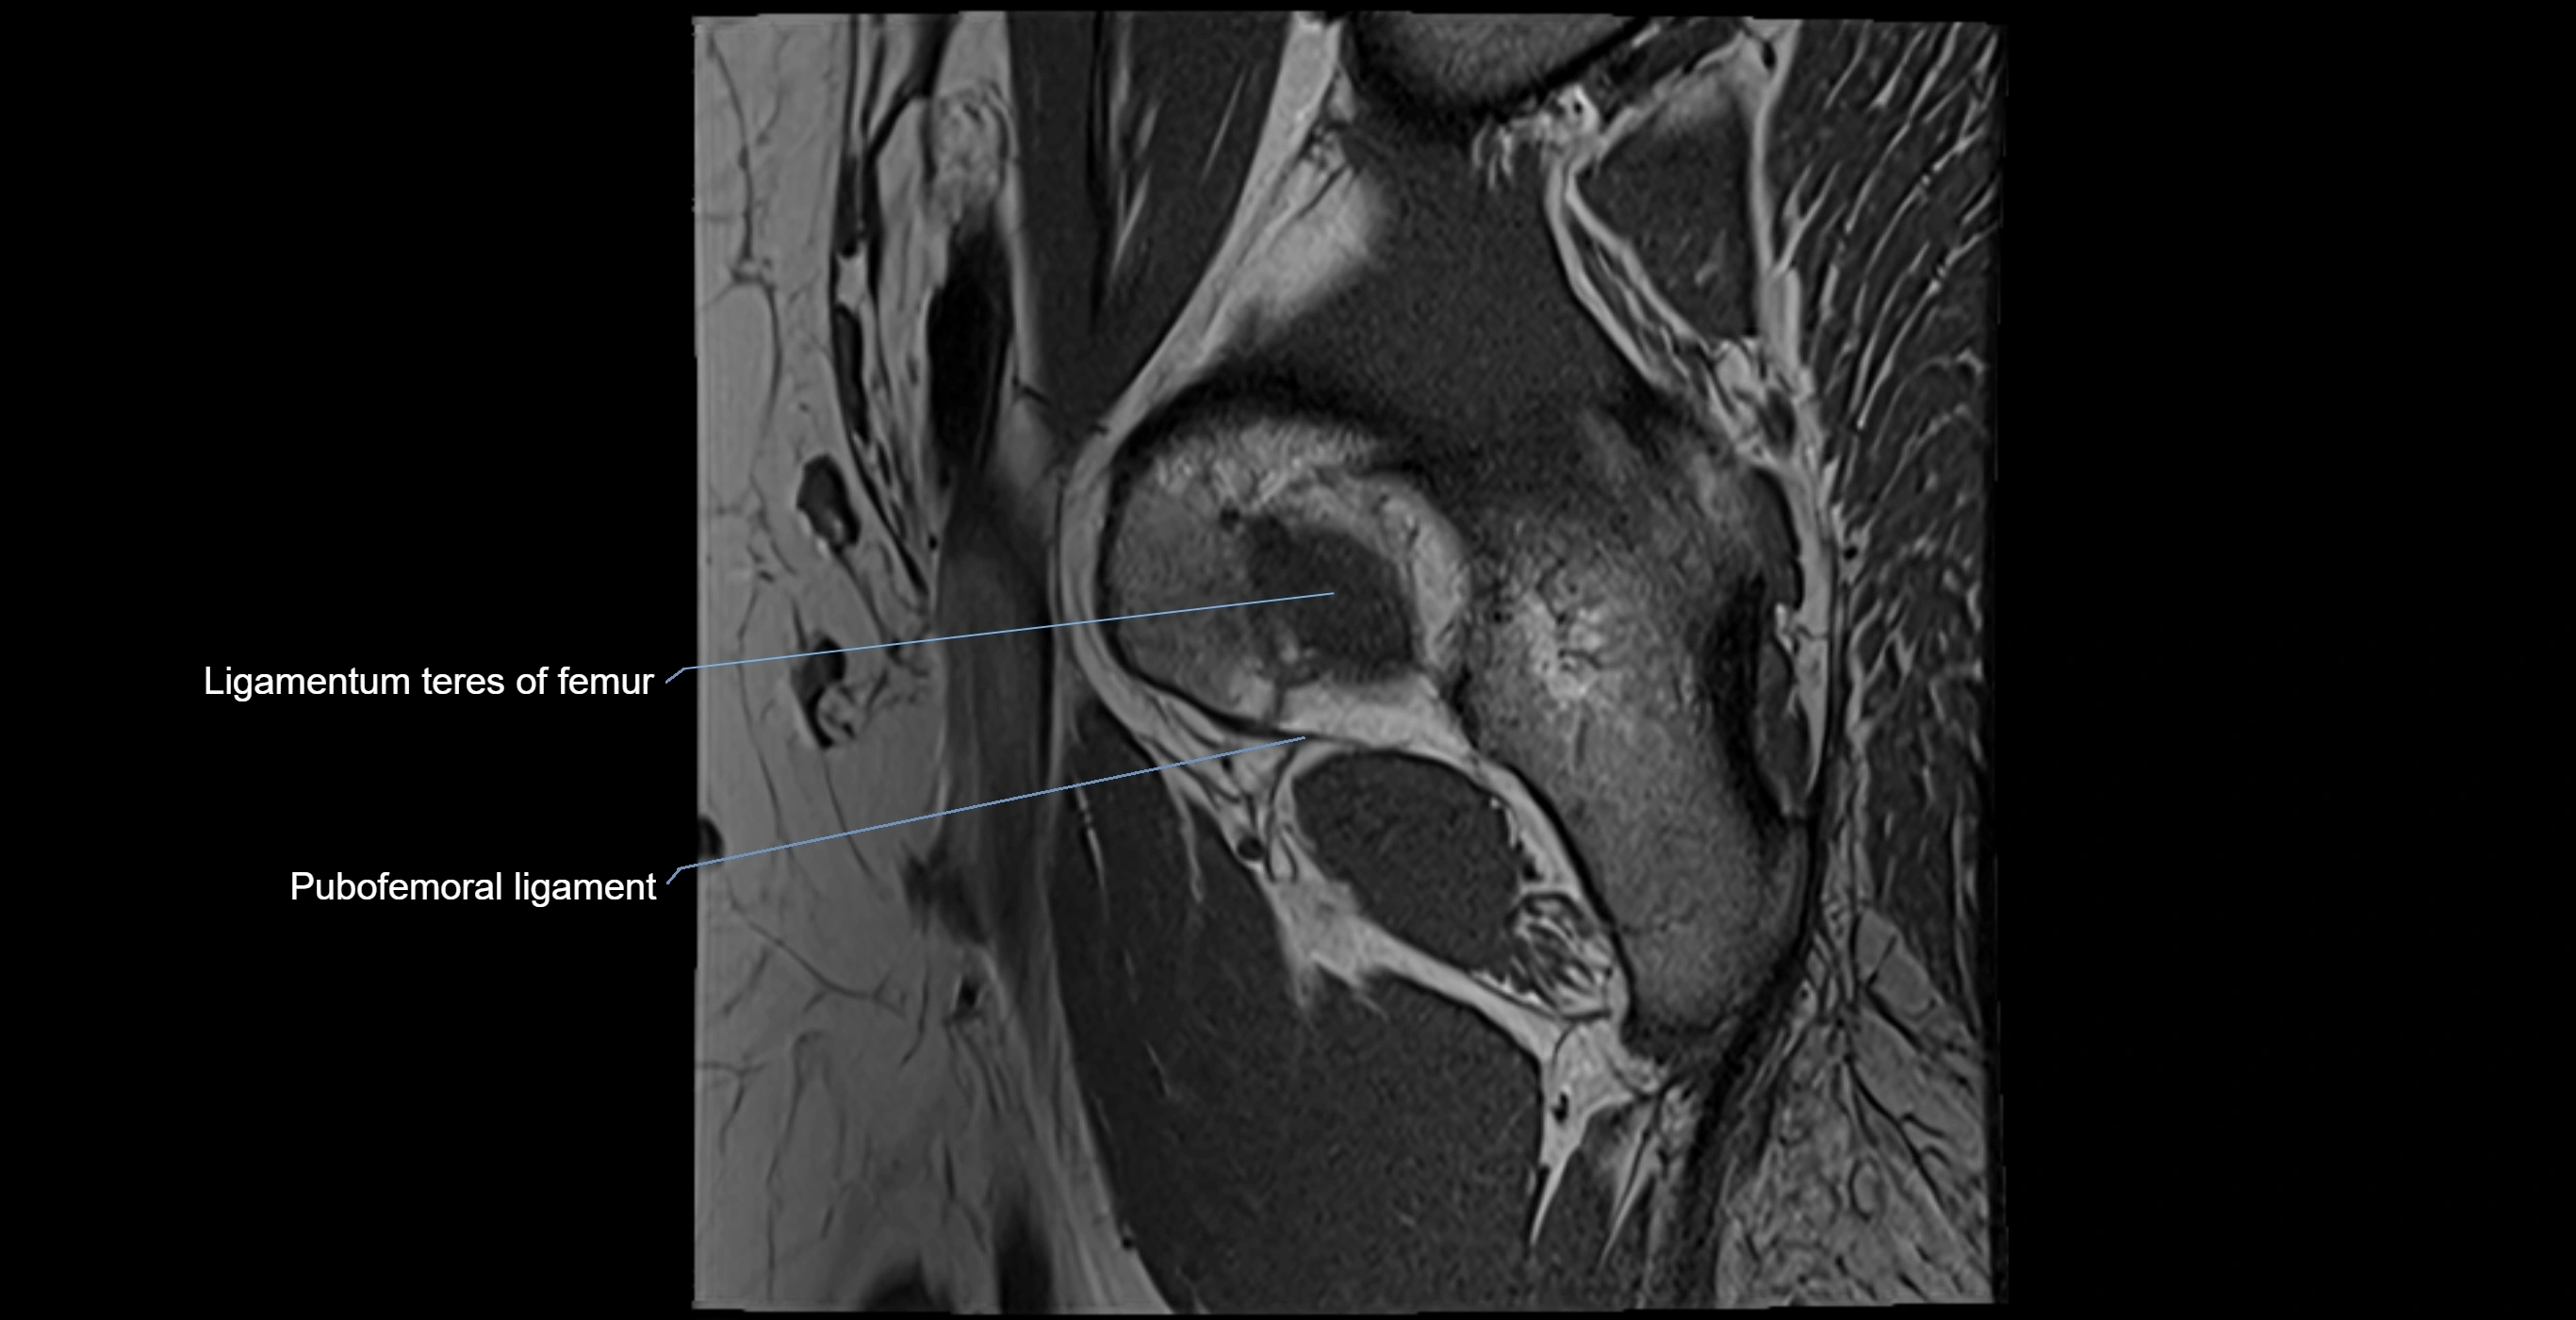

MRI Appearance

T1-weighted images:

• Labrum: low signal intensity (dark)

• Surrounded by intermediate signal joint fluid (bright on arthrogram)

• Tears: linear or focal areas of intermediate-to-high signal interrupting labral continuity

T2-weighted images:

• Joint fluid: bright, making labral tears visible as fluid extending into or around labrum

• Degeneration: may show areas of increased signal within labrum

MRI image

image